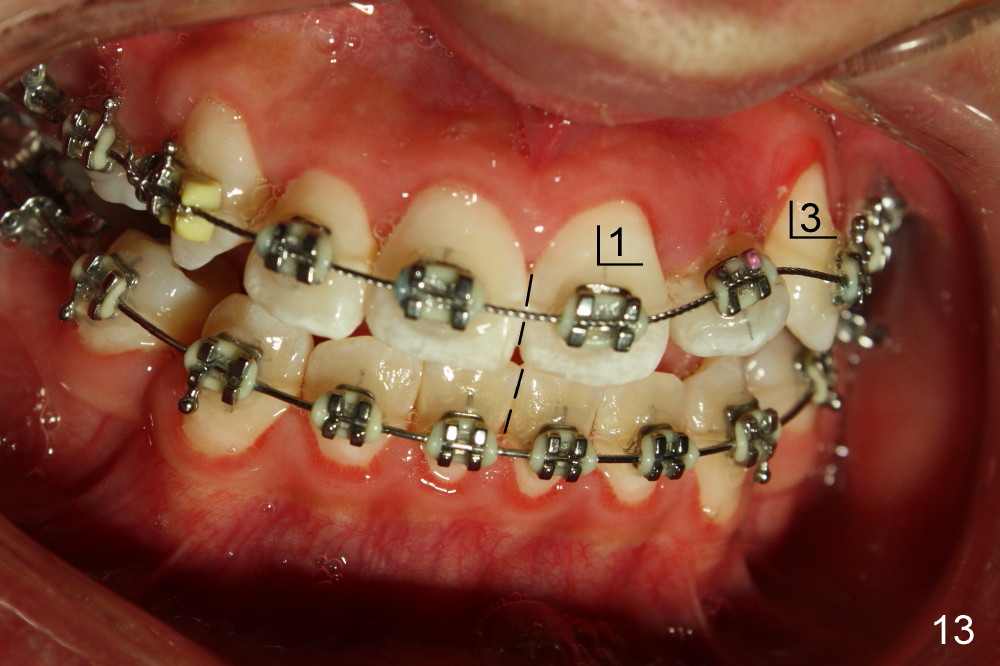

Seven months of treatment, the dental midlines coincide (Fig.13 dashed lines). Extraction spaces have been closed or being closed (Fig.13-15). UL 2 has been moved into the arch (Fig.13,15,16). But the alignment needs to be improved with arch wire sequence for a second time starting with .0175 twisted wire (Fig.13-16).

The alignment of UL2 improves one month of using .016x.022 ss wire with introduction of torque (total 14 months of treatment, Fig.17). The open bite (Fig.1-4, ignored), basically corrected nearly in the end of treatment (Fig.13-15), relapses < 2 years.